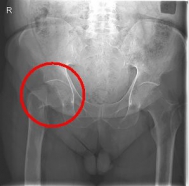

Femoral Neck Fracture

In addition to a thorough physical examination, radiographs of the pelvis and the affected hip are crucial for the diagnosis.

Images: Here is the supply of a dynamic hip screw shown.

In younger patients and a minor shift, the goal is to preserve the femoral head. The blood supply to the femoral head is at risk for medial femoral neck fractures, so that the fastest possible care should be sought if one wants to preserve the femoral head. Among others, the dynamic hip screw (DHS) is available for this purpose.